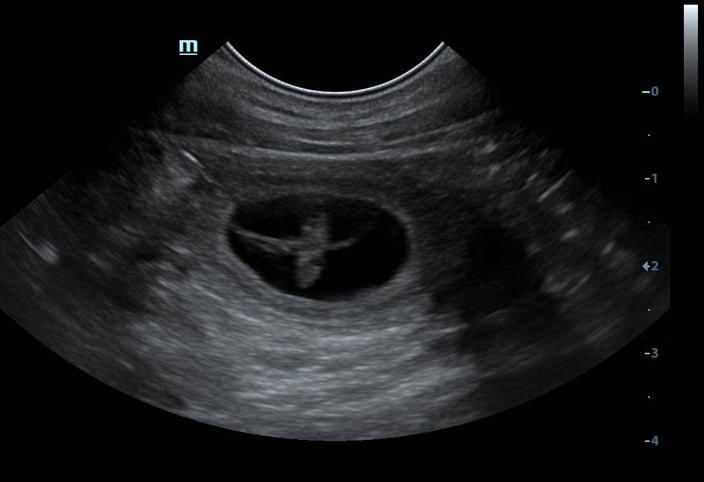

Die Verpaarung mit Vito war erfolgreich. Die Ultraschalluntersuchung (03.03.2025) lässt mehrere aktive Anlagen erkennen. Amira ist tragend.